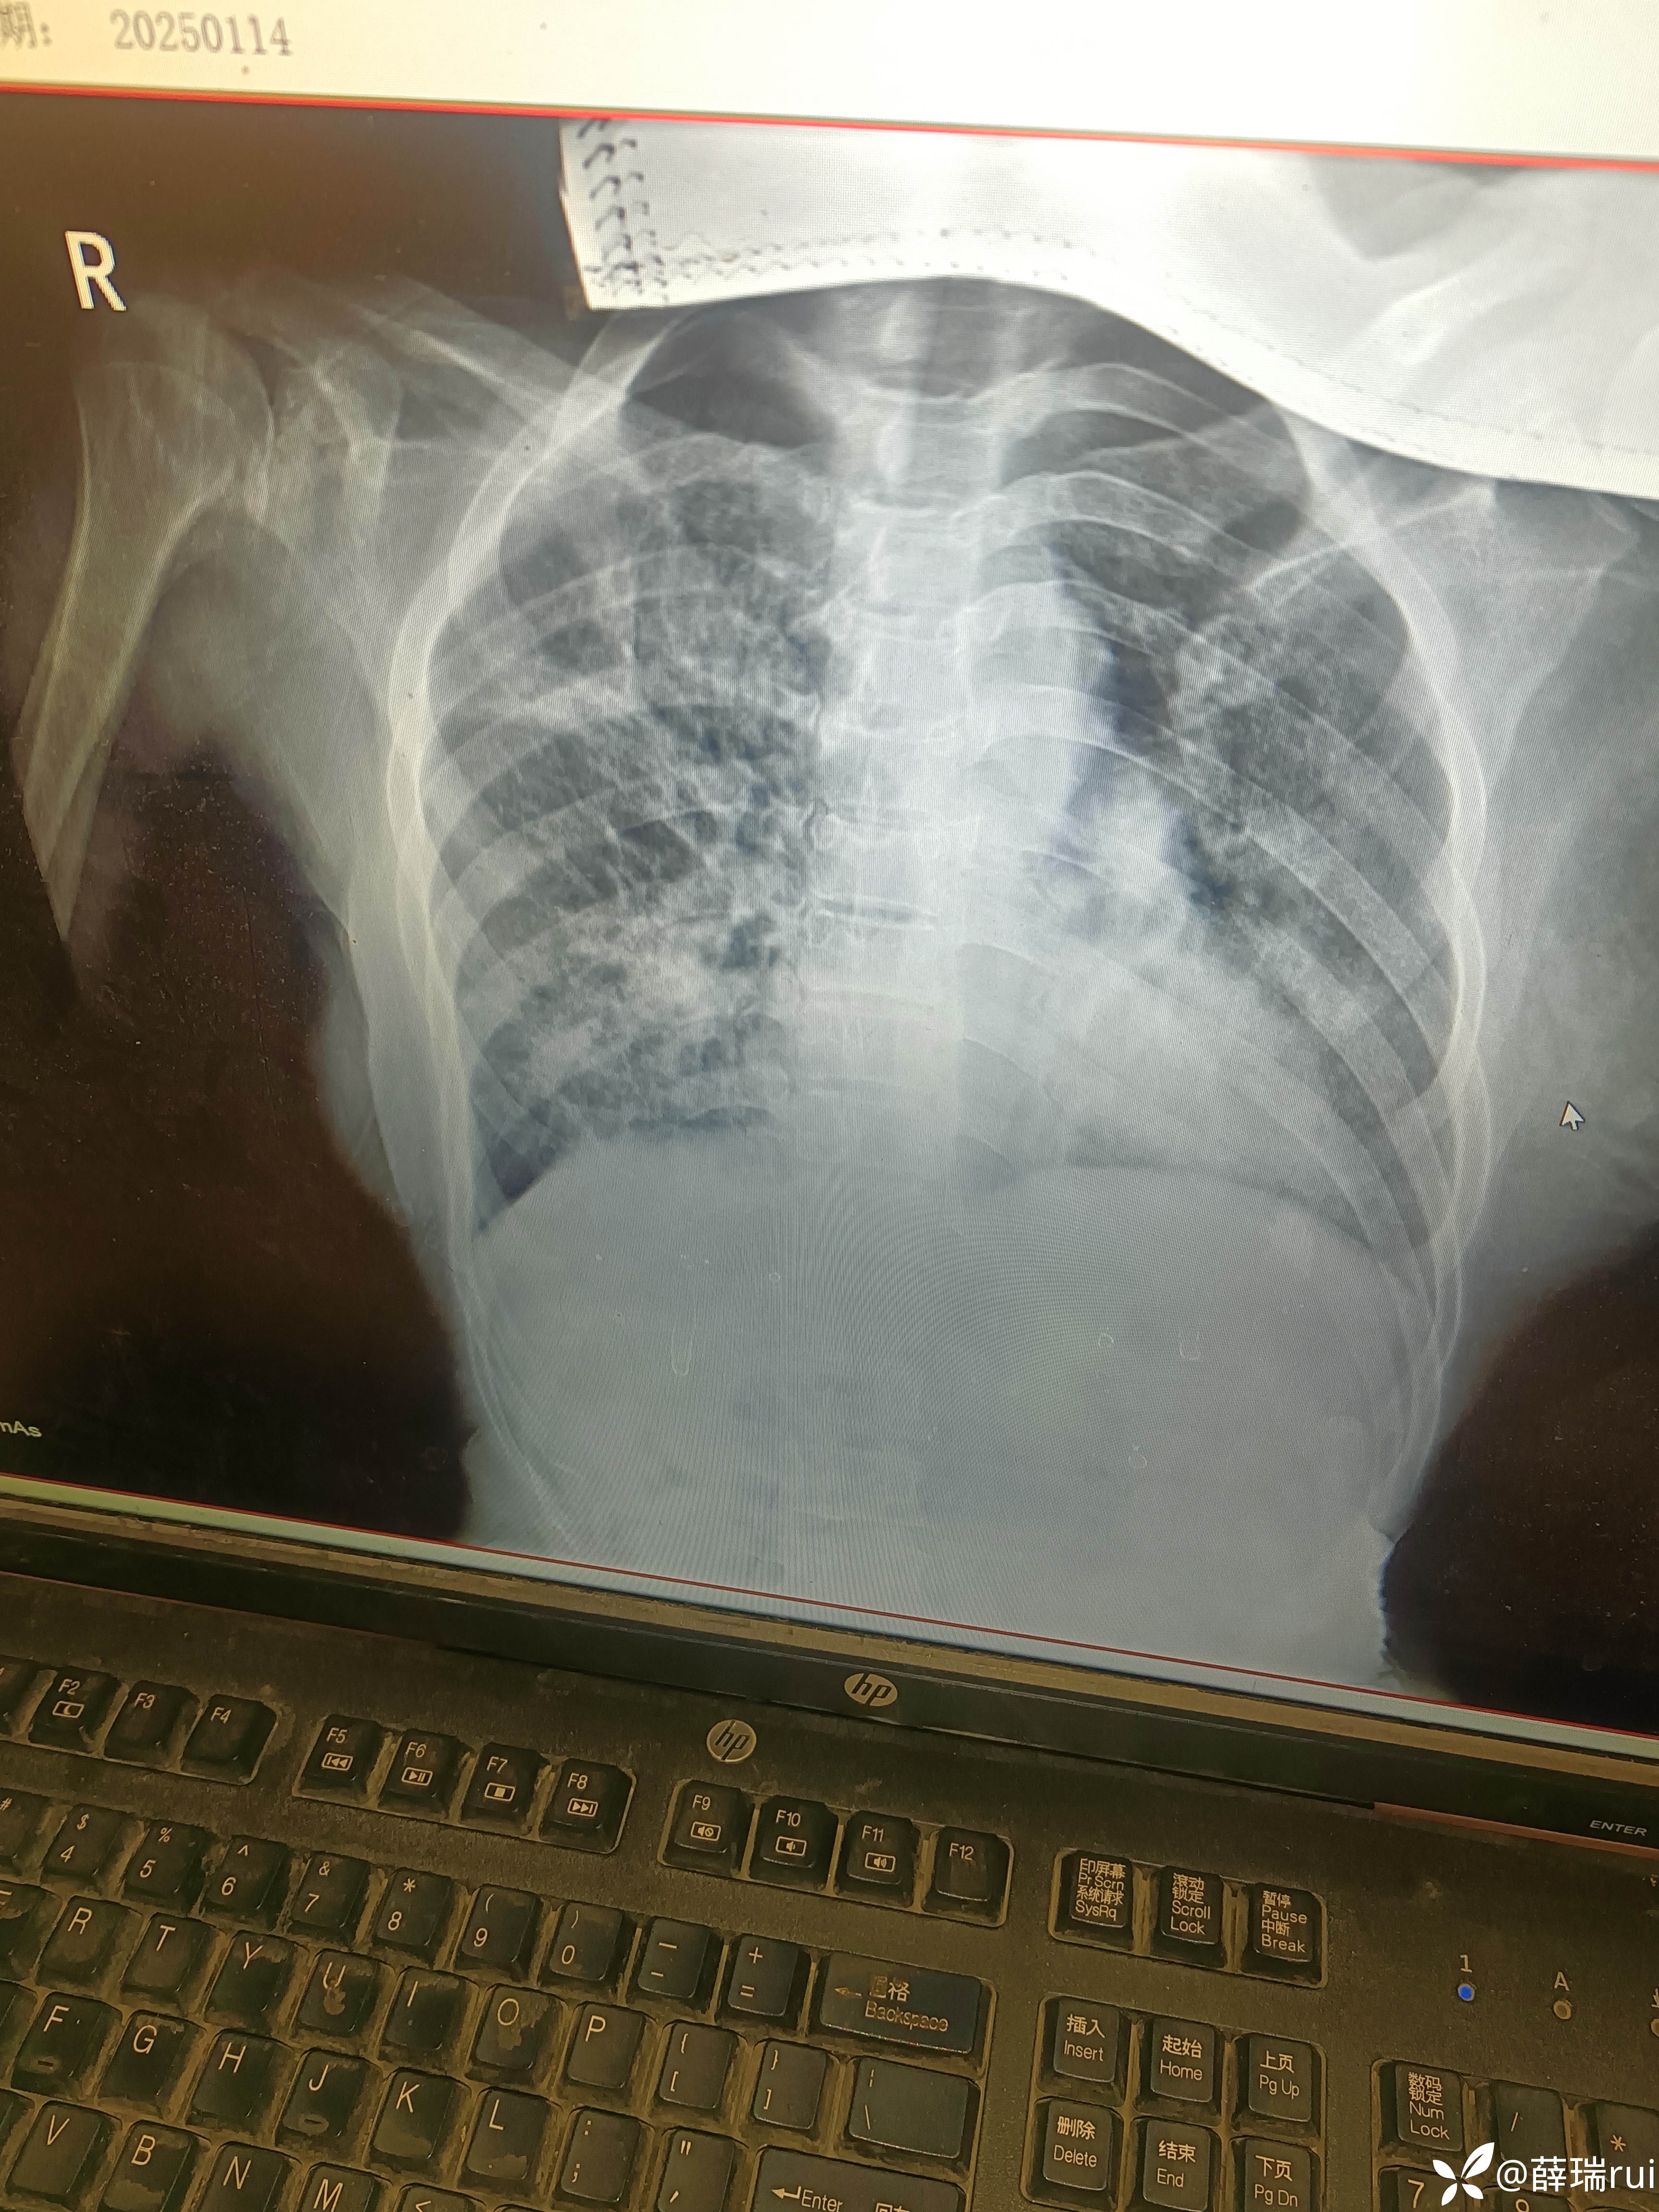

【患者信息】:女 55岁

【主诉】:咳嗽,纳差四肢手足指(趾)紫绀坏死3天。

【检查】

【治疗经过及结果】:阿莫西林克拉维酸钾,地塞米松